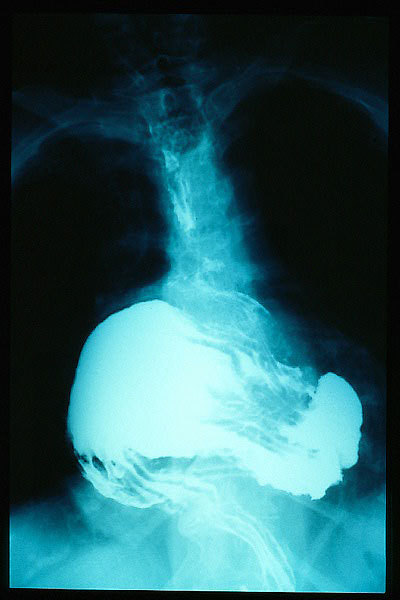

Hernia de hiato por deslizamiento al TGED.

Hernia de hiato por deslizamiento al TEGD.